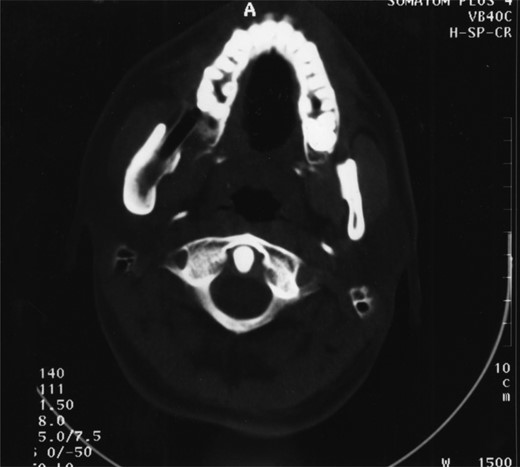

Radiographic examination over the following few months showed new bone formation and within 9 months of the initial biopsy the drain was expelled by formation of new bone (Fig. 3). One year after the commencement of treatment the patient was admitted for enucleation of the cystic remnant. At the time of this procedure a small cyst was removed from the right upper ramus and condylar neck, together, with a separate cyst associated with the lower right wisdom tooth. The patient made an uneventful post-operative recovery and histology revealed two KCOTs with a thick parakeratinized type of epithelium typical of radicular cysts.

Demonstrates bony infill with the nasopharyngeal tube in place.